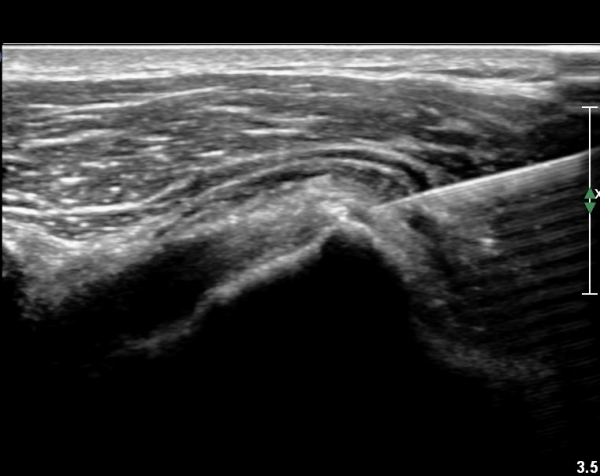

°ß°©ÇÏ±Ù°Ç ÇϺΠÁ¾´Ü¸é°Ë»ç¿Í Ⱦ´Ü¸é°Ë»ç °ß°©Çϱٰdz»  ¼®È¸È­ À½¿µÀÌ  °üÂûµÈ´Ù(»çÁø 3, 4).

°ß°©ÇÏ±Ù°Ç È¾´Ü¸é°Ë»ç»ó ¼Ò°áÀý ÇÊÁú°ñº¯È­¿Í °ß°©ÇÏ±Ù°Ç Áߺο¡ °í¿¡ÄÚ µ¢¾î¸®°¡ °üÂûµÇ°í

¼®È¸ À§ÂÊ(¸Ó¸®ÂÊ)ÀÇ ÈûÁÙÀÇ Àú¿¡ÄÚ º¯È­°¡ °üÂûµÈ´Ù(»çÁø 4, 5).